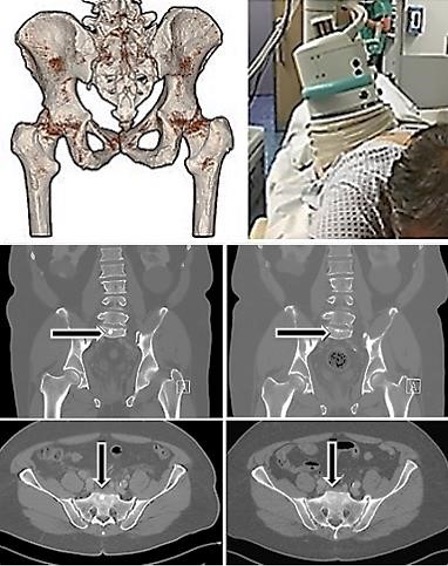

Based on patient‑specific FEM modeling, extracorporeal TMI focused shock wave therapy was directed to an iliac bone metastasis. Five TMI treatments (3 Hz, 0.11–1.41 mJ/mm², 1, 500–2, 000 impulses) were performed. One month after the final treatment, imaging revealed not only complete regression of the treated iliac metastasis but also disappearance of untreated bone metastases, including a previously visible metastasis in the sternum (Fig. 5). Periosteal pain resolved entirely.

Comparable abscopal effects were observed in four additional metastatic prostate carcinoma patients treated similarly (Fig. 6). In a representative case of a 68‑year‑old patient with disseminated pulmonary and osseous metastases, a subtotal regression of pulmonary metastases and faintly detectable sclerotic regression of bone lesions were observed one month after TMI therapy.

Fig. 6: Above left: Individual 3D-MRT/CT-DICOM determination for positioning of the treatment device. Above right: Positioning of the extracorporeal device for TMI treatment. Below left column: Bone metastases of a prostate carcinoma (arrows) before extracorporeal TMI focused shock wave treatments. Right column: The metastases significantly regressed after five TMI treatments performed on a metastasis in the pelvis region.